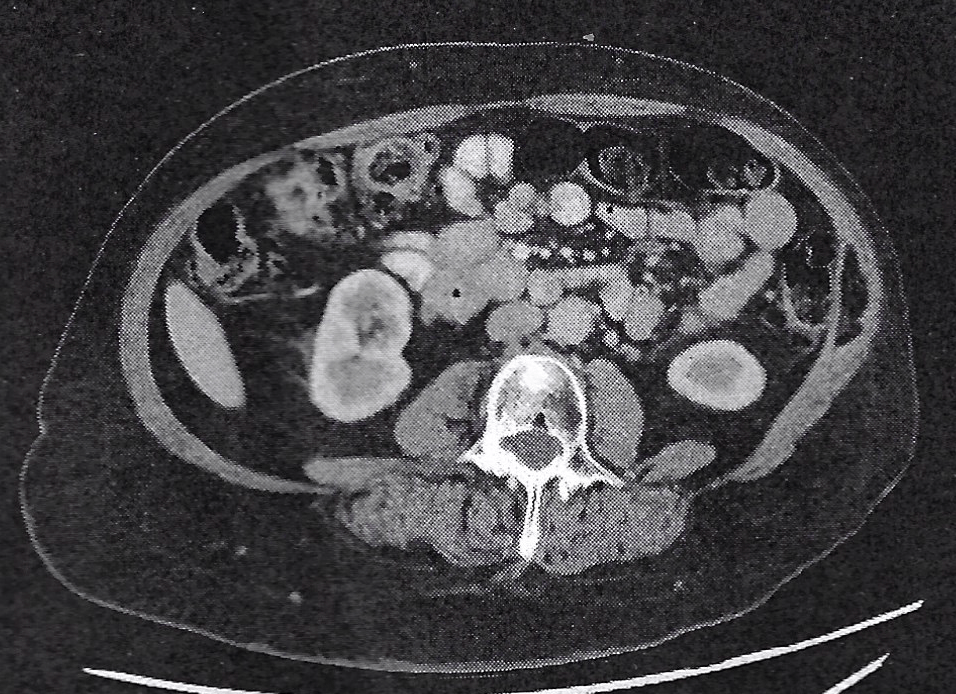

A few weeks ago, while waiting on pathology, I was musing about my colonoscopy results being ‘the other cancer shoe.’ Well, shoes do come in pairs, so I shouldn’t have been surprised when my doctor confirmed my colon lesion was malignant. To be precise: “Invasive poorly differentiated colorectal adenocarcinoma, BRAF Positive, dMMR, MSI-high.”

I can tell you now that hearing your second cancer diagnosis is nowhere near as terrifying as the first. I’m not making light of it, but ‘I know how this goes, I’ve done this before,’ did run through my head as a first reaction. It helped that my surgeon was excited: while it is an aggressive tumor profile, it is exceptionally responsive to immunotherapy, and were it not for my Cowden-like diagnosis, with a complete response to treatment, there would be an argument to forego surgery. Add to that, my CT made it clear this wasn’t metastasis from my endometrial cancer, and I consciously exhaled.